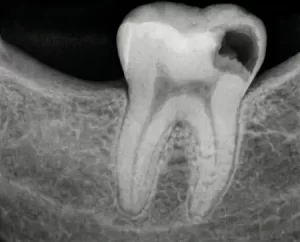

- Глубокий кариес. На данном этапе кариозный процесс носит обширный характер и добирается до пульпы. Не заметить проблему уже нельзя: возникает острая, порой нестерпимая боль даже в состоянии покоя. Могут развиться осложнения в виде пульпита, периодонтита. Если не вылечить кариес в стоматологии, это чревато потерей зуба.

Методы терапии определяются степенью повреждения зуба, формой заболевания и общим состоянием здоровья пациента. На цену лечения кариеса зубов влияют и другие факторы, включая локализацию очага. Для выявления точной причины болезни и назначения курса терапии проводятся визуальный осмотр полости рта и рентгенодиагностика.

- При среднем и глубоком кариесе без препарирования пострадавших тканей не обойтись. Это необходимо для профилактики дальнейшего распространения инфекции и прогрессирования болезни. После высверливания пораженных участков стоматолог приступает к пломбированию. В случае со средней стадией кариеса вылечить зуб можно за один визит. При глубоком кариозном процессе чаще требуется не менее 2-3 посещений.